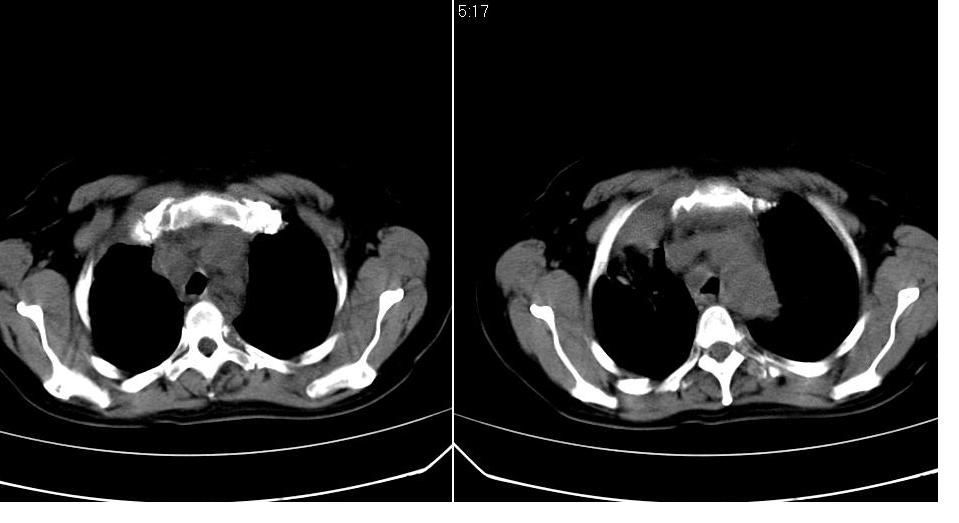

标题: CT16839:胸部CT平扫

女 50岁,在其他医院确诊肺癌.

肺癌,不能排除食管癌转移!

支持 右肺上叶肺癌并两肺及纵隔转移。

先考虑肺癌,淋巴瘤不排除